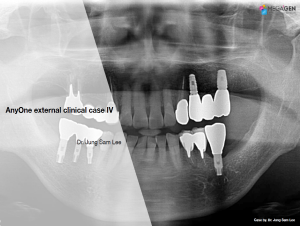

Aesthetic zone,AnyRidge,Clinical case,Dr. Achraf Souayah,Edentulous,Guided surgery,Immediate Placement,Mandibular Anterior,Mandibular Posterior,Maxillary Anterior,Maxillary Posterior,MEG-Rhein,MILA Kit,Overdenture system,Sinus Elevation